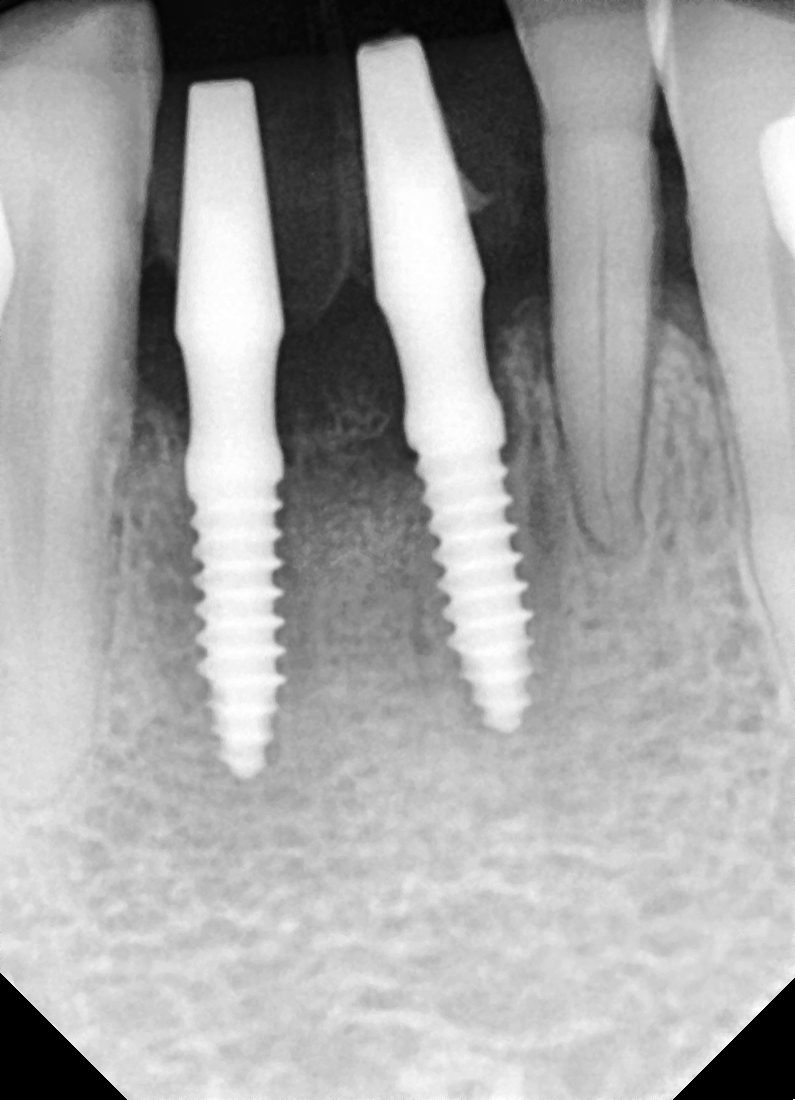

[임플란트] 제목 : 하악 전치부 골폭이 좁은 경우

일체형 임플란트로 . .